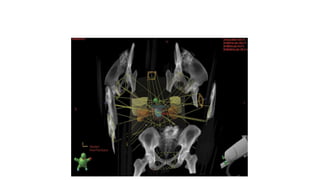

• Brachytherapy

With brachytherapy, radioactive sources (seeds or needles) are implanted

directly into the prostate gland, and sometimes into the surrounding tissues, to

deliver a high dose of radiation to the tumor while sparing, to the extent

possible, the bladder and the rectum.

Brachy therapy

• Types : Permanent/ Temporary

• Isotopes

• Why-

• Prostate has slow growth which remains localized for a long period

• Small t/t volume

• Potency well maintained with minimal complications

• Older patients>60 yr, less tolerace to high dose XRT

• Selection:

• Life expectancy >10 yrs

• Biopsy proven adenocarcinoma

• Stage T1 ,T2a

• Grade : Gleason sum 2-6

• PSA ≤ 10 ng/ml

• Prostate volume < 60 cc

• No e/o pelvic LAP/ Negative bone scan/ No prior TURP

• Brachy+ XRT: T2b , T2c, GS = 7-10, PSA > 10 ng/ml

• Brachy+ XRT+ Hormonal t/t : Initial large prostate > 60 cc

• TECHNIQUE

• TRUS and template guided implantation

• Templates: Syed- Neblett template or MUPIT (The Martinez Universal

Perineal Interstitial Template)